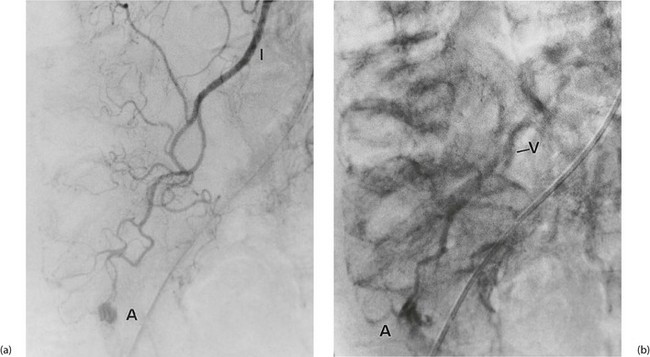

Investigation involves colonoscopy, usually once the bleeding has stopped. Occasionally an unsuspected carcinoma or polyp is discovered. In ulcerative colitis, the diagnosis is evident from the other symptoms and signs, and management depends on the success of medical treatment (see Ch. 28). Persisting large bowel haemorrhage which is less rapid but recurrent is usually due to angiodysplasias (see Ch. 29). Colonoscopy can be both diagnostic and therapeutic for bleeding angiodysplasia. If colonoscopy is negative, impossible or unsatisfactory, radioisotope scanning using the patient's own labelled red cells can be used; this has the advantage of identifying bleeding at rates as low as 0.05 ml/min. Highly selective arteriography is increasingly used in diagnosis of gastrointestinal haemorrhage but relies on much more rapid bleeding (greater than 0.5 ml/min) (see Fig. 19.12). At the time of arteriography, bleeding can be controlled with localised delivery of vasopressors or by coil embolisation.